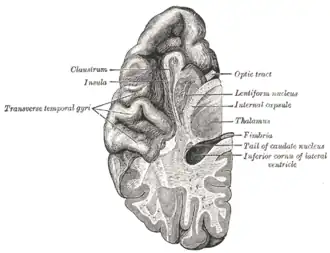

Section of brain showing upper surface of temporal lobe

Section of brain showing upper surface of temporal lobe -